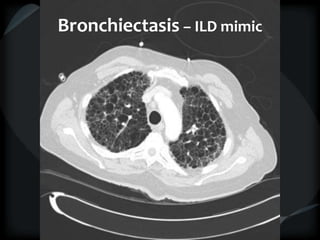

Bronchiectasis – ILD mimic

Bronchiectasis

Vessel at wall of cyst – signet ring

Cyst stacked in tubular orientation

Cyst stacked in branching pattern

Dilated, irregular, thickened airways

Mucus-filled airways

Diameter of peripheral airway to accompanying

artery = >1